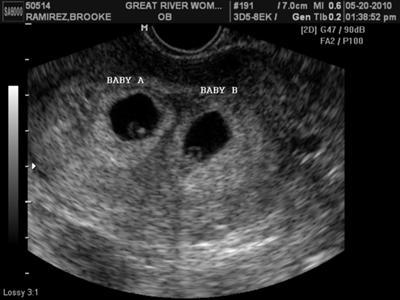

2 túi thai = 2 bánh nhau

2 buồng ối (2 yolksac) (1 bánh nhau 2 buồng ối)